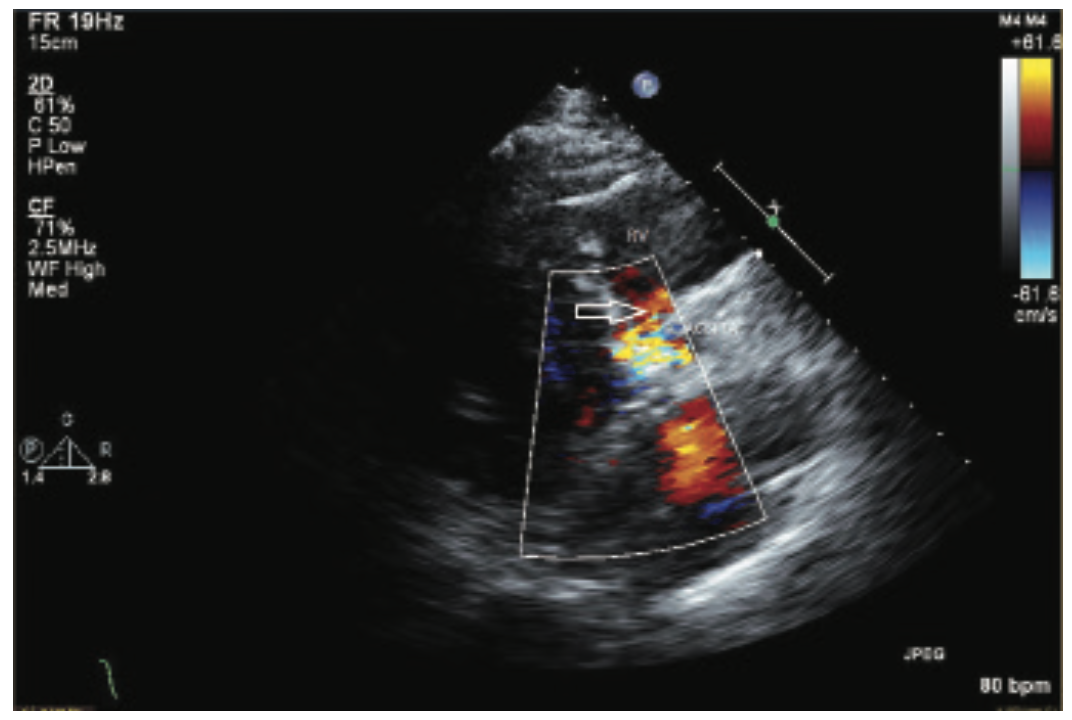

The TAVR procedure was performed one month later via right femoral access using the standard technique. Pre-dilatation with a 22 mm balloon was required, due to severe calcification of the valve leaflets. A 29 mm CoreValve Evolut (Medtronic) was advanced and appropriately positioned. A severe paravalvular leak was noted after valve deployment. Three serial dilatations were performed with 24 mm, 25 mm, and 28 mm balloons, respectively. Intraprocedural imaging revealed a mild paravalvular leak with a new severe central valvular leak, likely secondary to serial balloon dilatations. A second 29 mm CoreValve Evolut was subsequently deployed 3-4 mm above the initial valve with an excellent result. A transesophageal echocardiogram (TEE) revealed a small fistula between the aortic root and the right ventricle without a significant shunt. On the table, the patient developed complete heart block with a junctional escape rhythm. A temporary pacemaker was inserted, and he was monitored on telemetry throughout recovery. The following day, a permanent pacemaker was placed, secondary to persistent third-degree heart block. Post-operative TTE showed a normally functioning bioprosthetic valve, trace aortic regurgitation, calculated AVA 2.5 cm2, and a mean gradient of 6 mmHg. A fistula between the aortic root and RV was confirmed and unchanged. Mildly increased velocity across the pulmonic valve was noted without a change in RV pressure.

The patient remained asymptomatic post-procedure and was discharged on hospital day five. He had an otherwise uneventful hospital course. At 30-day follow-up, the patient denied dyspnea, orthopnea, or lower extremity swelling. He reported an increase in exercise tolerance and his physical exam did not yield any evidence of heart failure. Repeat TTE illustrated a stable aortic to RV fistula without hemodynamic changes. The patient continues to be managed conservatively with repeat imaging and clinical evaluation three years post procedure.